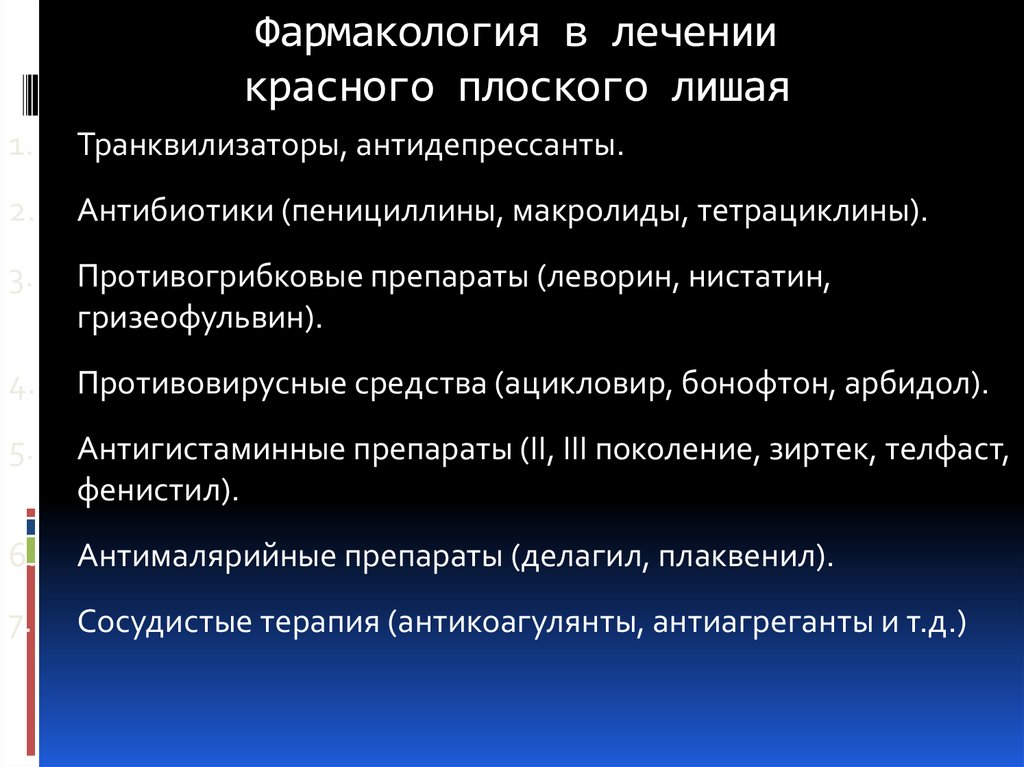

Фото Красного Плоского

Фото Красного Плоского 103 фото